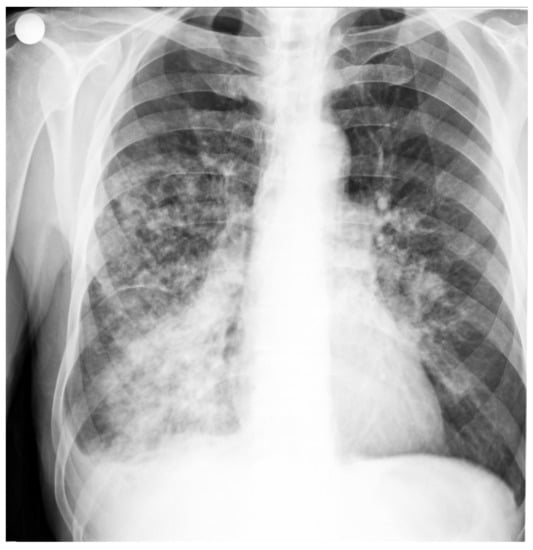

X-ray cord-lung: interstitial drawing of reticular micronodular type, intensely accentuated perihilar and bilateral infrahilar, with a tendency to bilateral hilum-basal condensation. Pulmonary hilum with enlarged projection area. Cord, aorta in normal limit (Figure 1).

Figure 1. Patient’s Rx cord-lung: interstitial drawing of reticular micronodular type, intensely accentuated perihilar and bilateral infrahilar, with a tendency to bilateral hilum-basal condensation.